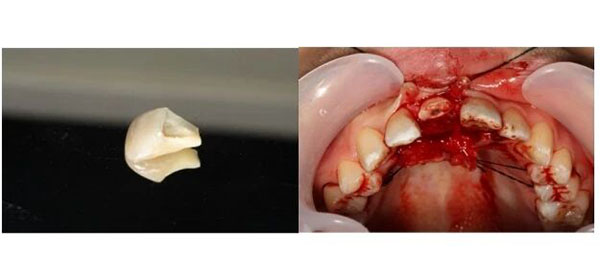

经过口腔检查,周伟伟看到,两颗门牙中那颗受伤更重的,确实是复杂冠根折:就是从牙冠到牙根都裂开了,牙神经也暴露了;而且折断的地方很深,一直延伸到牙龈下面。

最后,口腔急诊医生选择了一条更有挑战的路——在牙周翻瓣手术下,把折断的牙齿“接”回去:

先完成根管治疗,把牙齿内部清理干净。然后,在手术显微镜下,翻开牙龈,暴露出深藏在牙槽骨里的断端,用纤维桩像“钢筋”一样打进牙根里,再把断下来的牙冠原样粘回去。